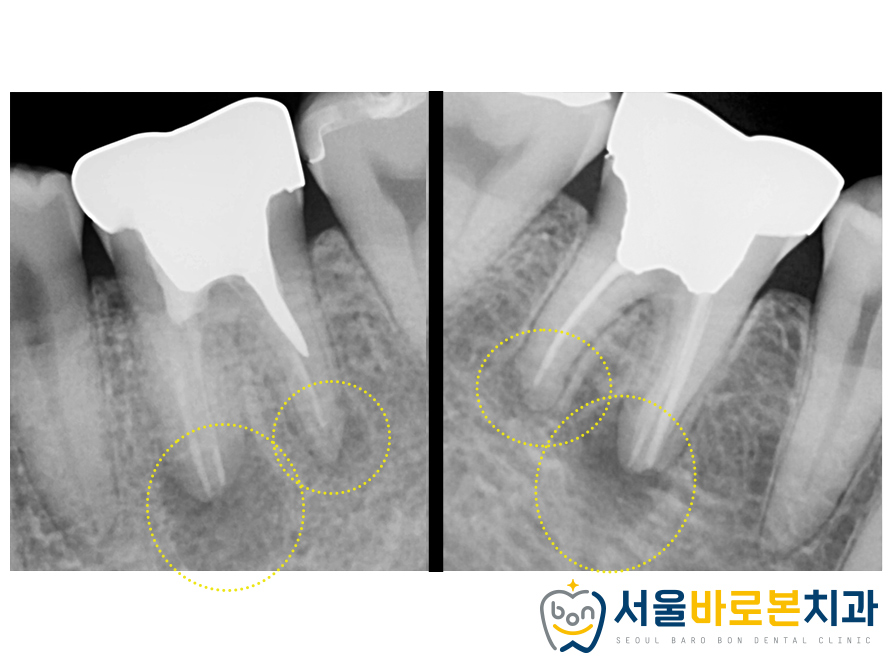

그런데 간혹 화살표 표시에

하얗게 나와보이는 부분을 보시고

치료가 잘못된거 아닌가요?

물어보시는 분들도 종종 계시는데요!

뿌리 끝으로 넘어간 하얀 재료는

보통 신경치료를 완료하였을 때 쓰이는 약재이며,

진료가 잘 완료되었다는 표시이기도 하므로

걱정하지 않으셔도 됩니다. ^^